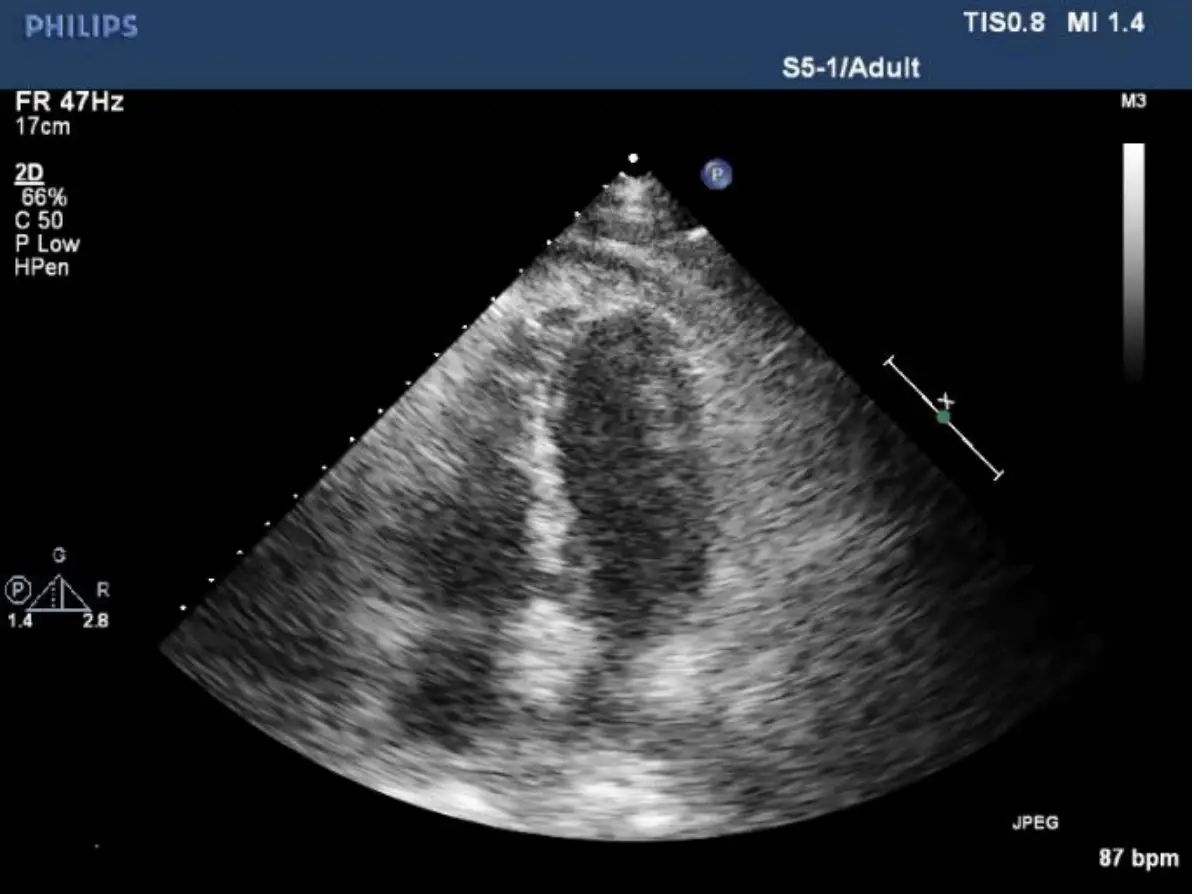

病人王先生現年88歲,有兩個月的雙腳浮腫及運動性呼吸困難,數度前往多家醫院求診,診療罔效。病人 有多年高血壓、高脂血、慢性腎臟病及前列腺肥大等過往病史。到診時意識清醒, T/P/R: 35.5 °C/99/18; BP: 106/83 mmHg; SpO₂: 92%。(ambient air); BH: 165 cm; BW: 66 kg; BMI: 24.2 kg/m² 理學檢查發現 顏面微腫,頸靜脈中度怒張,脈搏稍弱,並未有顯著Paradoxical pulse, 及Kussmaul sign,呼吸聲清 淨,心臟大小正常,心音略遠,P2稍強,Pericardial friction可疑,無肝、脾腫大,雙腳微腫。其心電 圖、胸部X光及其他影像檢查如圖:請問依照上列數個標的之理學檢查 (Targeted physical examination) 及實驗室所見,這位病人最可能的診斷是

心包積液及心臟壓塞(cardiac tamponade)的臨床表現、電圖特徵與多模態影像診斷。

影像分析:

- 胸部X光:心影擴大呈「水瓶狀」輪廓,心臟外形圓鈍平滑,肺野無明顯充血或水腫,符合大量心包積液造成的心影變化(en.wikipedia.org)